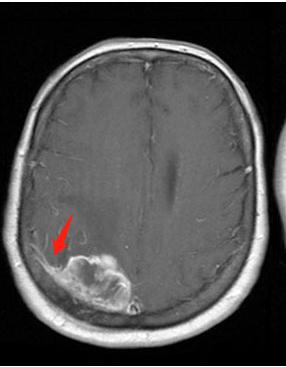

由于这种肿瘤起源于蛛网膜,所以在磁共振检查上面,我们能够看到肿瘤有条“小尾巴”,这是脑膜瘤连在蛛网膜上的“根”

这是位于嗅沟的脑膜瘤